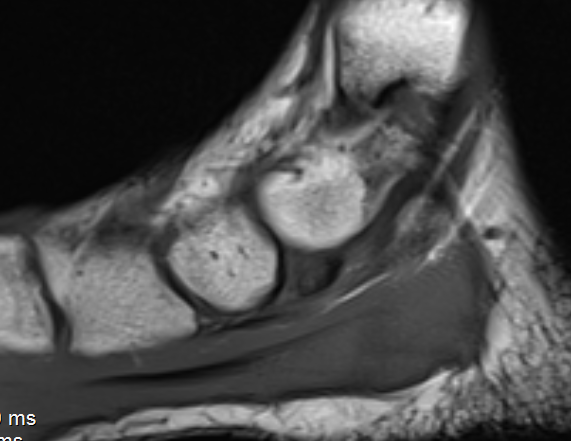

MRI

Show edema about a symptomatic accessory navicular